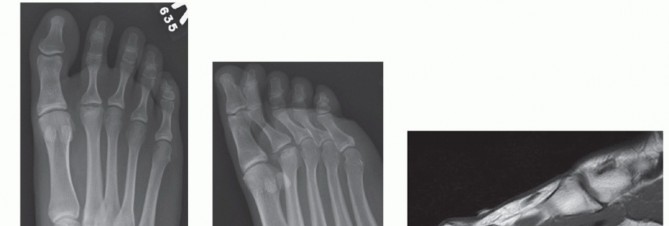

DEFINITION Freiberg infraction is an osteochondrosis of a lesser metatarsal head, most commonly involving the…